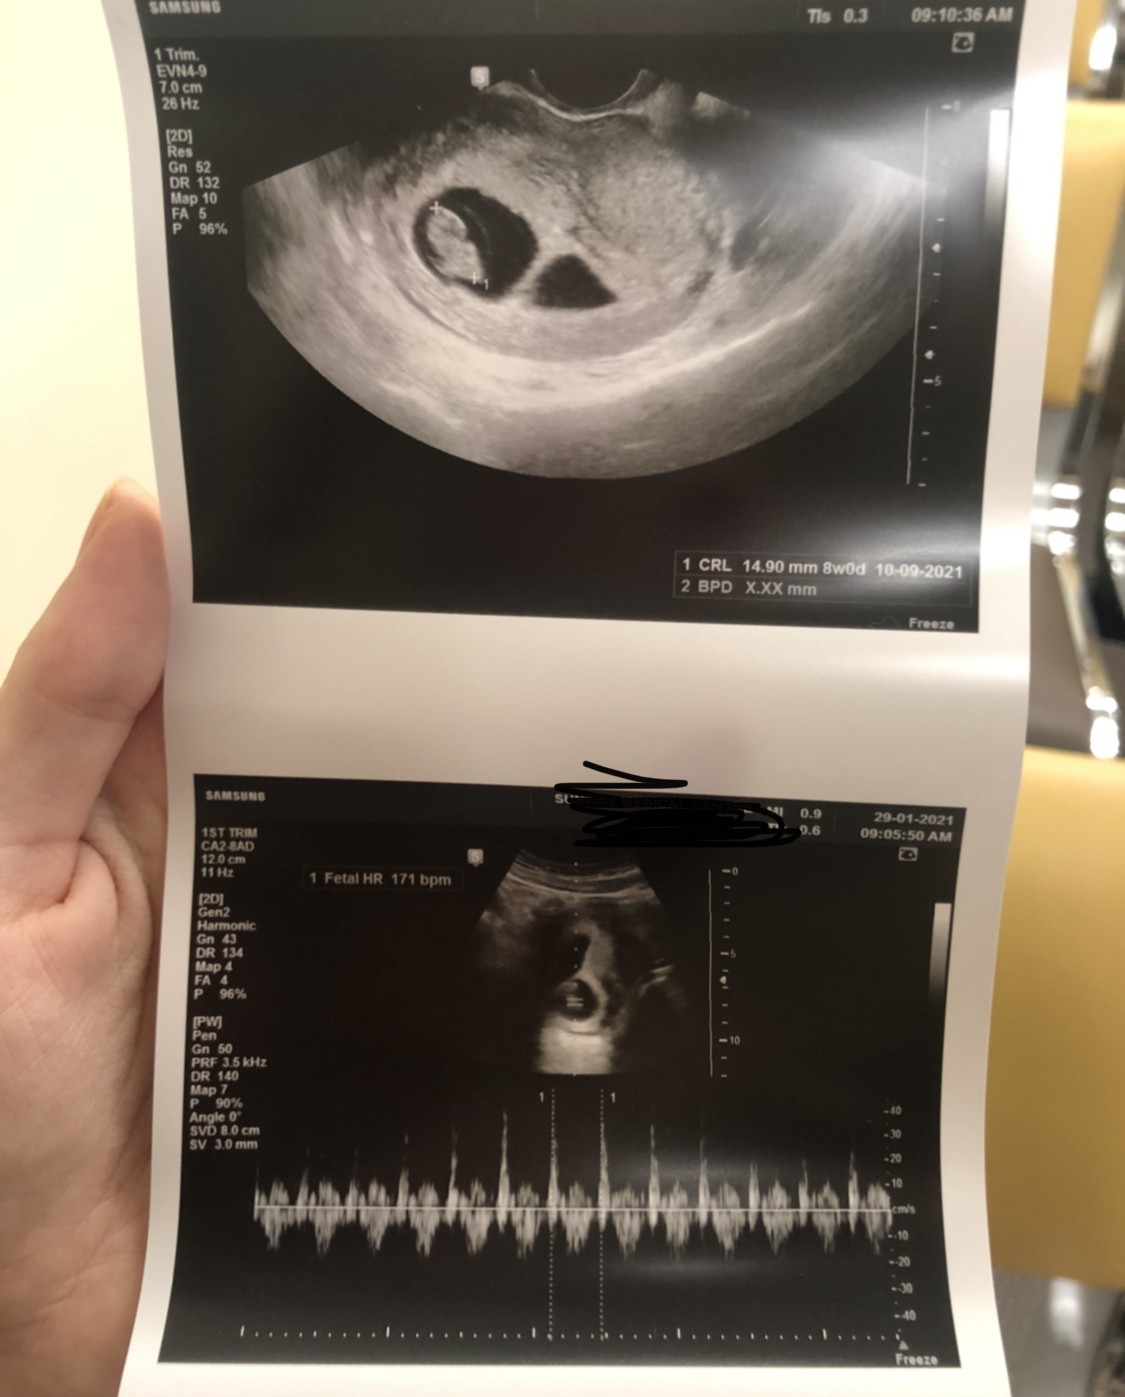

Poza tym usłyszałam serduszko, wszystko się zgadza, prawdopodobny termin 9/10.09❤️

uslyszalam serduszko!

wszystko jak na załączonym zdjęciu :)

Wiec mamy 8 tydzień! Następna wizyta za trzy tygodnie 😅